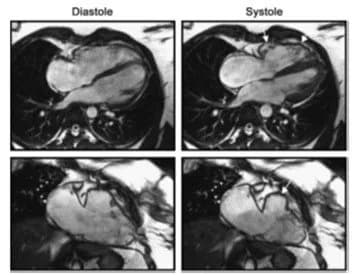

# Suy Tim và Vai Trò của Chụp Cộng Hưởng Từ Tim ## Giới thiệu về Suy Tim Suy tim là tình trạng khi tim không còn khả năng bơm máu đủ để đáp ứng nhu cầu oxy và chất dinh dưỡng của cơ thể. Đây là một trong những bệnh lý tim mạch nghiêm trọng, ảnh hưởng đến sức khỏe và chất lượng cuộc sống của hàng triệu người trên toàn thế giới. Suy tim có thể khởi phát từ nhiều nguyên nhân khác nhau và có thể để lại nhiều biến chứng nếu không được chẩn đoán và điều trị kịp thời. ![tim-suy-tim](image1) ## 1. Các Kỹ Thuật Cận Lâm Sàng trong Chẩn Đoán Suy Tim ### Nguyên Nhân Dẫn Đến Suy Tim Suy tim có thể phát triển từ nhiều tình trạng khác nhau như: - **Bệnh tim thiếu máu cục bộ**: Hoạt động của tim bị suy giảm do tình trạng thiếu máu, thường do mạch vành bị hẹp. - **Bệnh tăng huyết áp**: Làm tăng áp lực trong lòng mạch có thể dẫn đến tăng gánh nặng cho tim. - **Viêm cơ tim**: Tình trạng viêm nhiễm có thể làm tổn thương cấu trúc và chức năng của cơ tim. - **Bệnh lý cơ tim**: Những bệnh ảnh hưởng đến cơ tim, chẳng hạn như bệnh cơ tim dãn nở hoặc hạn chế. ### Các Tiêu Chí Chẩn Đoán Khi chẩn đoán suy tim, bác sĩ cần xác định những thông tin chi tiết về cấu trúc và chức năng của tim. Các tiêu chí này bao gồm: - **Phân suất tống máu của thất trái**: Là tỷ lệ phần trăm máu được tống ra khỏi tim trong mỗi nhịp đập. - **Cấu trúc thất trái**: Kích thước, hình dạng và chức năng tổng thể của thất trái. - **Tình trạng van tim và màng ngoài tim**: Bao gồm việc đánh giá hoạt động và thông số của các van tim cùng với trạng thái của màng ngoài tim. ### Phương Pháp Chẩn Đoán Truyền Thống **Siêu âm tim** là phương pháp phổ biến nhất hiện nay để chẩn đoán suy tim. Nó cho phép quan sát trực tiếp cấu trúc và chức năng tim. Tuy nhiên, siêu âm tim có một số hạn chế như không thể cung cấp hình ảnh chi tiết về mô cơ tim và không đánh giá được những vùng tim bị tổn thương nhiều. ![cộng-hưởng-từ-tim](image2) ## 2. Tính Ứng Dụng của Chụp Cộng Hưởng Từ Tim ### Ưu Điểm của Chụp Cộng Hưởng Từ Tim (CMR) Chụp cộng hưởng từ tim đang trở thành công cụ đắc lực trong việc chẩn đoán suy tim nhờ nhiều ưu điểm vượt trội: - **Độ chính xác cao**: Cung cấp hình ảnh 3D chi tiết về cấu trúc, chức năng và mô cơ tim. - **Xác định căn nguyên của suy tim**: Dựa vào hình ảnh mô tả rõ ràng, các bác sĩ có thể phân biệt giữa suy tim do nhồi máu cơ tim và suy tim do các nguyên nhân khác. - **Khả năng theo dõi diễn tiến bệnh**: CMR có khả năng quan sát và ghi nhận những thay đổi nhỏ nhất trong cấu trúc và chức năng tim theo thời gian. ### Hạn Chế Của CMR Mặc dù CMR có nhiều ưu điểm, việc ứng dụng kỹ thuật này trong thực tế vẫn còn một số hạn chế do chi phí cao và cần các thiết bị kỹ thuật hiện đại. ![an-toan-cmrt](image3) ## 3. Tính An Toàn Của Kỹ Thuật Chụp Cộng Hưởng Từ Tim Chụp cộng hưởng từ tim được coi là phương pháp tương đối an toàn. Tuy nhiên, vẫn có những yếu tố cần cân nhắc: - Những bệnh nhân có các dụng cụ cấy ghép từ tính trong cơ thể, chẳng hạn như máy tạo nhịp tim, cần thận trọng khi sử dụng phương pháp này do từ trường mạnh có thể làm ảnh hưởng các thiết bị. - Các bệnh nhân suy giảm chức năng thận cần được giám sát chặt chẽ khi sử dụng chất tương phản, để tránh nguy cơ phát triển bệnh xơ hóa hệ thống do chất tương phản gây ra. ## Kết Luận Chụp cộng hưởng từ tim là phương pháp hiện đại, có độ chính xác và an toàn cao trong chẩn đoán và theo dõi suy tim. Mặc dù có những hạn chế về mặt kinh tế và cơ sở vật chất, nhưng đây vẫn là một công cụ hữu ích giúp cải thiện chất lượng điều trị suy tim. Trong tương lai, việc mở rộng áp dụng CMR có thể tạo ra bước ngoặt lớn trong điều trị bệnh lý tim mạch, giảm thiểu nguy cơ và nâng cao chất lượng cuộc sống cho người bệnh.